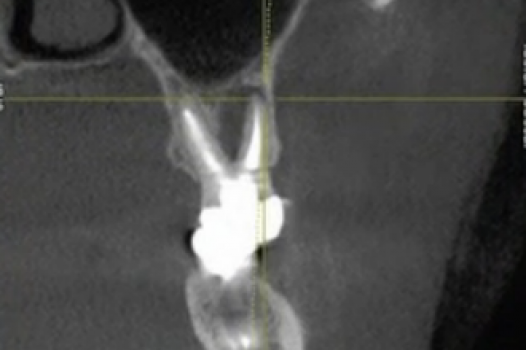

TMJ CBCT Imaging

Jaw joints will remodel if the dental bite causes joint postural compression or overloading.  CBCT imaging is part of the diagnosis to assist in building a solution for “TMJ symptoms”.

Neck CBCT Imaging

Accessing the skeletal neck and lower jaw balance is part of a TMD diagnosis.  The alignment of the dental bite will impact the alignment of the cervical vertebra in the neck.